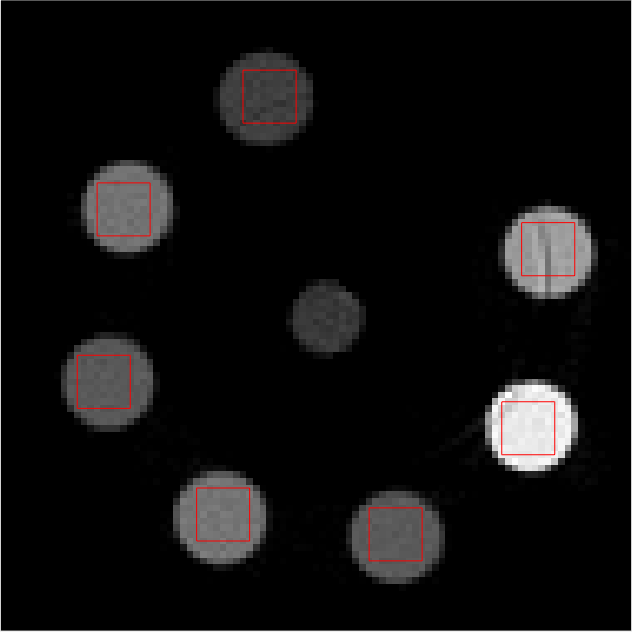

Individual reconstructions from every bin were first performed with scalar MBIR. This furnished 555 LAC images, each from a different energy bin. 101010 slices of each LAC image volume were used to compute \mathcal{M}. The mixing matrix was computed from ROIs shown in red in Fig 2. The following equation must be satisfied ideally

Refer to caption

(a)

(b)

(c)

(d)

(e)

Figure 2: Middle slice of LAC image reconstruction of each energy bin sinogram for mixing matrix estimation. Display window [0, 0.1]

LABEL:sub@fig:En1 Bin1:7.019.0keV7.019.0𝑘𝑒𝑉7.0-19.0\ keV, LABEL:sub@fig:En2 Bin2: 19.029.0keV19.029.0𝑘𝑒𝑉19.0-29.0\ keV, LABEL:sub@fig:En3 Bin3: 29.038.8keV29.038.8𝑘𝑒𝑉29.0-38.8\ keV, LABEL:sub@fig:En4 Bin4: 38.851.1keV38.851.1𝑘𝑒𝑉38.8-51.1\ keV, LABEL:sub@fig:En5 Bin5: 51.182.6keV51.182.6𝑘𝑒𝑉51.1-82.6\ keV